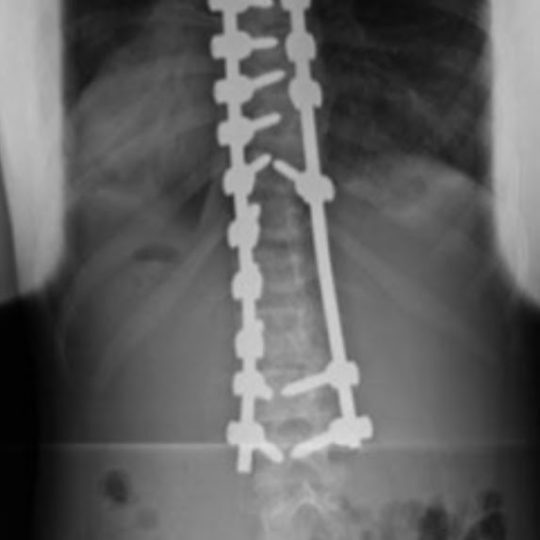

https://youtu.be/UP2khJYApQY The Harrington Rod is a stainless steel surgical device used in Scoliosis spinal fusion surgery. In this video, we discuss how the Harrington Rod works, complications and risks, and alternative treatments for Scoliosis. We also discuss Tethering Scoliosis Surgery, indications for scoliosis surgery, potential side effects of scoliosis surgery, alternative treatments including CLEAR non-invasive scoliosis methods and Scolibrace. Learn more about Tethering Surgery at Children’s Hospital of Philadelphia Shriner’s and Institute for Spine and Scoliosis. https://www.chop.edu/treatments/vertebral-body-tethering https://www.spineandscoliosis.com/ Learn more Scolibrace and Non-Invasive Scoliosis Care at www.drjhartley.com Or contact us at: Hartley Chiropractic and Scoliosis Center 1740 Tree Blvd #115 St. Augustine, FL 32084 904-679-3233